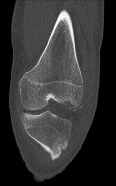

Question 5:

A 32-year-old female presents with progressive knee pain. Imaging reveals an eccentric, lytic, epiphyseal lesion in the proximal tibia extending to the subchondral bone without a sclerotic margin. Biopsy confirms multinucleated giant cells intermixed with mononuclear stromal cells. If targeted medical therapy is initiated prior to surgical curettage, what is the primary mechanism of action of the preferred agent?

Correct Answer: Monoclonal antibody binding to RANK ligand (RANKL)

Explanation:

The clinical and radiographic presentation is classic for a Giant Cell Tumor (GCT) of bone. Denosumab is a monoclonal antibody frequently used as neoadjuvant or primary medical therapy for aggressive or unresectable GCTs. It binds specifically to RANKL, preventing it from interacting with RANK receptors on osteoclast precursors and the giant cells themselves, thereby profoundly inhibiting osteoclastogenesis and tumor-associated bone destruction.